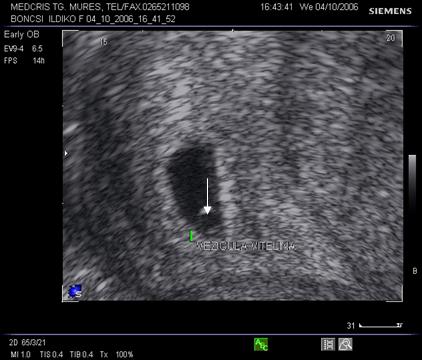

Fig nr. 8. Sarcina 5 sapt la ecografia transvaginala :sac ovular cu vezicula vitelina evidenta marcata cu sageata, retrouterin ovar chistic

Fig nr.9. Vezicula vitelina, marcata cu sageata, la ecografia transvaginala, sarcina 5 sapt.